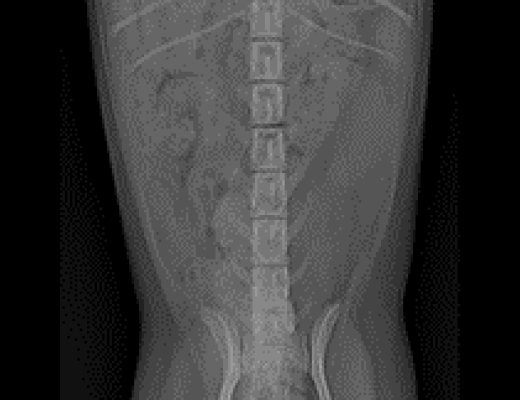

요관 폐색의 진단에 있어서 가장 중요한 검사는 방사선, 초음파, CT 검사 등의 영상 진단입니다.

· 방사선 검사

방사선 검사는 방사선 상에서 확인될 수 있는 결석의 개괄적인 위치 파악에 있어 중요하게 작용합니다. 방사선 상 명확하게 보이는 결석 또는 이차적인 신장의 비대 소견이 확인되게 되면, 실제 신장 및 요관에서 발생한 형태 변화를 확인하기 위해 초음파 검사를 진행하게 됩니다.